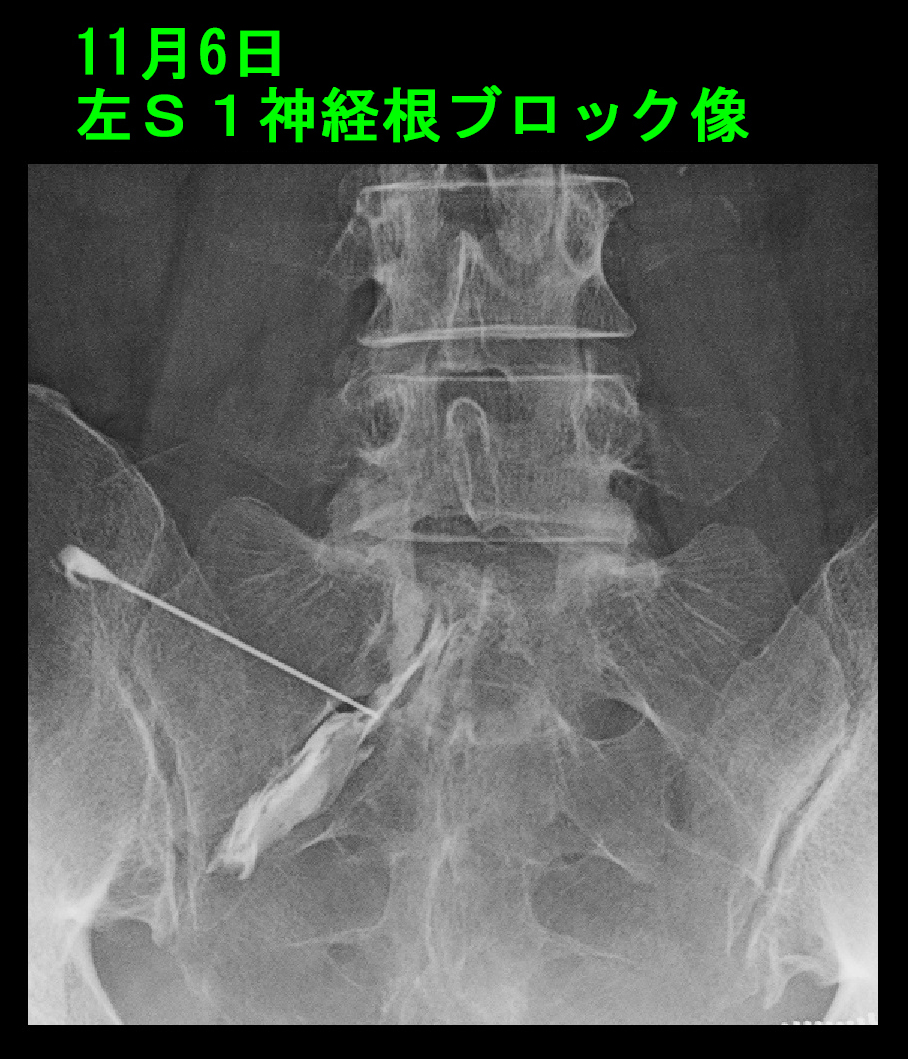

54才女 Xp2.jpg

私は自信を持っていたのですが、11月6日の再診時の評価では、VAS8→7→8という経過で、全く効果がなかったと評価すべき経過でした。